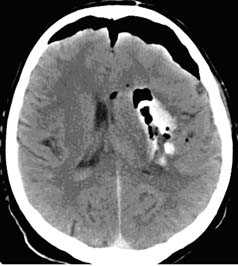

Применение компьютерной томографии в нейротравматологии существенно изменило представление о возможностях диагностики различных черепно-мозговых повреждений. КТ является в настоящий момент «золотым стандартом» - наиболее информативным методом обследования больных с черепно-мозговыми травмами и позволяет в самые короткие сроки судить о механизмах возникновения поражения мозга, его характере, распространенности, выраженности отека и дислокации мозга, а также динамике этих изменений.

- выявить наличие внутричерепной гематомы (её характер, локализацию, размеры),

- выявить наличие очага ушиба головного мозга (его локализацию, размеры, характер, наличие геморрагического компонента),

- определить степень сдавления или дислокации головного мозга объемным процессом,

КТ с внутривенным контрастированием (КТ-ангиография) по неотложным показаниям, как правило, не выполняется. Показанием к такому исследованию является обнаружение на нативных томограммых внутримозговых гематом, локализующихся в местах возможного разрыва аневнизмы.